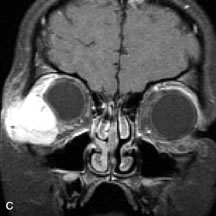

PATIENT PREPARATION Before MRI is performed, patients must be screened and prepared to avoid the potential hazards associated with the strong magnetic field. Patients who have ferrous aneurysm clips or cardiac pacemakers, who depend on life-support equipment, or who retain a possible metallic intraocular foreign body are not candidates for this imaging modality. MRI cannot be performed on obese patients who cannot fit into the bore of the magnet. Patients who are claustrophobic may not tolerate a prolonged period of study within the confines of the magnet, whereas others might do well if given a mild sedative. All worn metallic objects (e.g., necklaces, watches) should be taken off, credit cards set aside, and eye makeup removed before entering the room containing the magnet.5,20,34,35,36 NORMAL ORBITAL ANATOMY T1-weighted images provide the best anatomic details of the orbit because they display superior contrast resolution between normal structures (see Fig. 8). The vitreous has a long T1, resulting in an intermediate signal similar to brain, whereas the crystalline lens and sclera appear dark because of a longer T1 and short T2. The extraocular muscles, like all skeletal muscles, demonstrate a moderately long T1 and short T2 and highly contrast with the intense signal of the surrounding orbital fat (adipose tissue has an extremely short T1). The lacrimal glands appear as mottled areas of reduced intensity of the signal from the orbital fat in the lacrimal fossa. The optic nerves are seen with the same signal intensity as brain white matter and are hypointense relative to the orbital fat because their Tl is longer than the Tl of fat but shorter than the Tl of water. Cortical bone is not well delineated because it contains little free water, yielding minimal signal in MRI, and thus appears dark on all pulse sequences. This feature explains why MR images of the orbital apex and intracanalicular portion of the optic nerves are superior to comparable CT scans. Partial volume averaging of the bones in these regions obscures soft tissue details on CT images, whereas MRI reveals the signals only from the soft tissue structures with no cortical bone input. Bone marrow, on the other hand, is seen as a relatively intense signal because of its high fat content (see Fig. 8).37,38 T2-weighted pulse sequences are not ideal for imaging normal anatomy; however, they are particularly useful in revealing pathologic conditions (see Fig. 9). T2-weighted studies are most easily recognized by a bright vitreous signal. ORBITAL DISEASES Vascular Lesions Cavernous hemangiomas appear as well-circumscribed, smooth, usually intraconal masses that are isointense to muscle on T1-weighted images and hyperintense on T2-weighted images (Fig. 12). Patchy early enhancement is typically followed by diffuse, more homogeneous enhancement.39 The internal architecture of the mass, including septation and internal vasculature, may often be appreciated with high-quality orbital imaging.40 Lymphangiomas consist of ectatic vascular channels within a connective tissue stoma with varying degrees of lymphoid cellularity. On MRI, these tumors are typically poorly circumscribed, multicompartmental, and heterogeneous, often showing cystic dilations with fluid levels (Fig. 13). The signal characteristics within lymphangiomas vary considerably, reflecting cystic and solid components and the varying paramagnetic characteristics of blood at different stages of degradation.40–42 Acute hemorrhage appears hypointense on both T1- and T2-weighted formats. Methemoglobin present in subacute hemorrhage (3 to 14 days) leads to hyperintense signal on both T1- and T2-weighted images.41 A small percentage of lymphangiomas appear radiologically indistinct from orbital cavernous hemangiomas.43 Orbital varices are venous malformations that expand with increased systemic venous pressure, such as with Valsalva maneuvers. Because rapid acquisition of images during a Valsalva maneuver is important in imaging such a lesion, conventional or spiral CT is currently the modality of choice.44 MRI is an excellent modality for demonstrating enlargement of the cavernous sinus and dilation of the superior ophthalmic vein in patients with high-flow carotid-cavernous fistulas (Fig. 14).37MRA may be helpful in the evaluation of the venous outflow pattern. The rapidly flowing blood in these vascular structures carries the excited protons out of the section before they can be imaged, resulting in their dark appearance.5 In low-flow dural arteriovenous malformations, MRA may help define the arterial feeding vessels.45 Neural Lesions MRI is more effective than CT in delineating the intracranial optic nerves, chiasm, and optic tracts and, for this reason, is the preferred imaging modality in the evaluation of optic nerve disorders. The spatial relationships and image contrast of the orbital tissues with intraorbital optic nerve tumors is comparable between the two imaging modalities. The normal nerve is isointense to brain and appears enlarged and kinked owing to infiltration of an optic nerve glioma on T1-weighted images. Gliomas appear hyperintense on T2-weighted images and may be heterogeneous owing to cystic areas within the tumor. Contrast enhancement is variable.46 Intraorbital and intracranial optic nerve sheath meningiomas are usually isointense to cortical gray matter on Tl-weighted images and remain isointense on proton density studies (Fig. 15). Gd-DTPA is useful in delineating the intracranial extension of optic nerve meningiomas.7,47 The hyperostosis of bone and calcification associated with meningiomas are not demonstrated as well on MRI studies as on CT scans.20,37 Gd-DTPA–enhanced MRI also appears promising in the study of the permeability of the blood–brain barrier in selected optic neuropathies.22,48 MRI may reveal an enlarged optic nerve and some degree of contrast enhancement in cases of optic neuritis.49 Muscle Disorders Extraocular muscle enlargement in patients with thyroid-associated orbitopathy is demonstrated equally well with CT and MRI studies. However, the superior tissue contrast on MR images reveals better details of the relationships of the optic nerve to the thickened muscles at the orbital apex (Fig. 16).50 In addition, MRI may be able to differentiate between muscles that are enlarged as a result of edema and active inflammation and those enlarged because of fibrosis by their T2 relaxation times.21 Quantitative MRI was not found to be accurate in predicting the success of low-dose orbital irradiation.51 However, a muscular index relating the diameters of the rectus muscles to the bony orbital dimensions was useful in predicting optic nerve compression.52 MRI is also effective in imaging orbital tumors of mesenchymal origin, such as rhabdomyosarcoma, particularly in the assessment of extension into the anterior and middle cranial fossae (Fig. 17).37 The lack of any pathognomonic radiologic features necessitates rapid orbital biopsy when rhabdomyosarcoma is suspected. Osseous Lesions In general, CT is the imaging modality of choice when details of quantity and quality of bone are needed; however, abnormalities of bones can be detected indirectly by MRI. Cortical bone appears black (signal void) on MR images because of its low proton density and free-water content. The absence or discontinuity of the signal void of the orbital walls may represent bony destruction or fracture. Hyperostosis associated with prostate metastases or meningioma is visualized as areas of black smudging.50,53 Diseases in which the bone is replaced by pathologic tissues with a high free-water content, such as fibrous dysplasia, are well demonstrated on MRI. An intermediate signal intensity on T1-weighted images and hypointense signal on T2-weighted images is representative of fibrous dysplasia. Enhancement on post–Gd-DTPA MR scans is seen and is more evident in areas that are less mineralized.54 Cystic Lesions Dermoid cysts appear as rounded, well-defined lesions typically contiguous with an orbital bony suture. The high-intensity signal on T1-weighted images is attributed to the sebaceous-produced lipid contents (Fig. 18).31,50 Mucoceles may demonstrate a hypointense or hyperintense signal on MR images, depending on the concentration of proteinaceous or inflammatory fluid components. The integrity of the bony walls of the expanded sinus cavities cannot be assessed on MR as well as by CT.37,50,55,56 A high-signal intensity on Tl- and T2-weighted images is characteristic of orbital chronic hematic cysts because of the blood-breakdown products within the cysts.57 Trauma Although soft tissue relationships are usually better demonstrated on MRI, the evaluation of craniofacial bony trauma is preferable with CT. For example, prolapse of orbital fat through a fracture site and hemorrhage of adjacent tissues are demonstrated in an MR image, but the actual fractured bone is not imaged. Three-dimensional MRI of the orbit in subacute trauma has been described,58 although its precise role is not currently established. MRI has been suggested to be superior to CT in detecting intraorbital wooden foreign bodies.59,60 In a series of penetrating orbital injuries with organic foreign bodies, however, MRI was able to identify the foreign body in only four of seven cases.61 With an in vitro model for wood foreign body, McGuckin and colleagues concluded that CT was the imaging modality of choice.62 A careful history and, in selected cases, plain films to rule out a metallic foreign body are crucial before MRI is considered in patients with periocular trauma. MRI is particularly helpful in the detection and characterization of subperiosteal hematomas of the orbit (Fig. 19). They are most commonly seen in the subperiosteal space of the superior orbit as well-defined masses following a traumatic injury. The signal intensity varies depending on the acute, subacute, or chronic nature of the hematoma, based on the stage of blood degradation. Fresh hemorrhages are hypointense on T1-weighted images and hyperintense on T2 images. Hematomas that are 1 to 7 days old are hypointense on both T1- and T2-weighted images. T1-weighted images of hematomas more than a week old are hyperintense due to the oxidation of deoxyhemoglobin to methemoglobin, whereas the T2 images remain hypointense.63 Metastatic Tumors Breast carcinoma metastatic to the orbit has been demonstrated to be hypointense to the surrounding orbital fat on T1-weighted studies and hyperintense on T2-weighted images and has an affinity to the extraocular muscles (Fig. 20).50,64 The MRI characteristics of prostate carcinoma metastatic to the orbit have been described as involving the greater and lesser wing of the sphenoid, orbital roof, and optic canal. Diffuse bone hypertrophy with isointense or slightly hyperintense tissue on T1-weighted images represents the osteoblastic carcinomatous bone infiltration. Contrast enhancement is variable on T1-weighted and fat-suppressed images.65 Most other metastatic tumors also have a lower intensity signal on T1-weighted images and appear to displace or infiltrate normal orbital structures; however, their signal characteristics are variable on T2-weighted MR images.66 Many metastatic tumors demonstrate bright contrast enhancement with Gd-DTPA. Infectious Disorders MRI findings of preseptal and orbital cellulitis typically include increased signal intensities on T2-weighted images of the eyelids and orbital fat, respectively, due to the increased water content of the tissues. Since most cases of bacterial orbital cellulitis are associated with paranasal sinusitis, hyperintense signals of the affected sinuses may also be found on T2-weighted images as well as enhancement of polyps and granulation tissue on postgadolinium T1-weighted MR images. Subperiosteal abscess formation may occur due to contiguous spread of infection from the paranasal sinuses and appear on MRI as an area of intermediate signal on T1-weighted and proton-weighted MR images. The abscess may appear slightly hyperintense compared with muscle on T2-weighted scans with the necrotic contents having the greatest intensity.67 MRI and MRV are more sensitive than CT in revealing cavernous sinus thrombosis. Engorgement of the cavernous sinus, extraocular muscles, and ophthalmic veins is seen with hyperintensity of the thrombosed sinuses evident on all pulse sequences. The enlarged, thrombosed superior ophthalmic vein appears less hypointense than the normal contralateral ophthalmic vein, and hyperintensity within the lumen of the vessel may be seen on T1- and T2-weighted MR images.68 Inflammatory and Lymphoproliferative Lesions Inflammatory conditions of the orbit, both idiopathic (inflammatory pseudotumor) and those of known causes, have been found to be hypointense to fat and isointense to muscle on Tl-weighted studies and isointense or slightly hyperintense to fat on T2-weighted images (Fig. 21).50,64,69 The more fibrous or sclerosing varieties have less signal intensity on T2-weighted images. Marked enhancement is seen in pseudotumor infiltrates after gadolinium administration.70 The same signal characteristics are demonstrated in patients with Tolosa-Hunt syndrome, with mass lesions seen in the cavernous sinuses and orbital apices.71 Lymphomas have MRI characteristics similar to those of inflammatory lesions in that they are hypointense to fat and isointense to muscle on T1-weighted images (Fig. 22). They may appear hyperintense to fat on T2-weighted images, perhaps owing to less fibrosis than that seen in orbital inflammatory pseudotumor, although this is not a consistent finding.31,50,66 Lymphoid tumors typically enhance moderately after contrast injection. Unfortunately, studies have shown that tumor density and homogeneity are similar between inflammatory and malignant orbital infiltrates, and MRI cannot differentiate these lesions.72,73 Lacrimal Gland Tumors Lacrimal gland lesions present special problems in diagnosis and management. Pleomorphic adenoma (benign mixed tumor) should not be biopsied, but rather excised in toto. On the other hand, for lymphoma and inflammatory infiltrates, incisional biopsy is more appropriate than complete excision of the lacrimal gland. Thus, preoperative clinical and radiologic evaluation are especially crucial in planning appropriate surgical management. Pleomorphic adenomas demonstrate long T1 and T2 signal characteristics. They may show heterogeneity on T2-weighted images74 and moderate to marked enhancement with contrast.75 Signal characteristics of adenoid cystic carcinoma include hypointensity to fat on T1-weighted images, hyperintensity to fat with increased T2 weighting, and isointensity to fat on proton density-weighted studies (Fig. 23).31,75 Secondary bony alterations of the lacrimal fossa associated with lacrimal gland tumors, such as remodeling (benign mixed tumor) or destruction (adenoid cystic carcinoma), are seen indirectly on MR images; however, bone windows on CT scans provide better delineation of these changes. In contrast to the round or globular appearance of benign or malignant epithelial tumors of the lacrimal gland, lymphoproliferative tumors usually appear to be molding or draping onto the globe and the surrounding bony orbit. LACRIMAL DRAINAGE SYSTEM DISORDERS MRI with surface coils provides excellent spatial resolution and tissue-specific signal intensities of the lacrimal drainage system. These parameters have been found useful to more accurately demonstrate the extent of lesions in the lacrimal sac and differentiate long-standing mucoceles from solid tumors than CT.76 Physiologic studies in patients with tearing disorders now include MR dacryocystography, in which Gd-DTPA is either placed topically in the conjunctival fornix or injected by cannulation into the lacrimal sac. They provide a detailed morphologic and functional analysis of the lacrimal excretory system; however, they are no more sensitive than digital-subtraction dacryocystography or CT dacryocystography.77–79 INTRAOCULAR TUMORS On MRI, uveal melanomas have a typical appearance that helps to differentiate them from other primary and secondary intraocular tumors as well as choroidal detachments. Pigmented melanomas are hyperintense on Tl-weighted images, hypointense on T2-weighted studies, and hyperintense on proton density–weighted examinations (Fig. 24).30,31,50,80–82 These signal characteristics have been attributed to the paramagnetic properties of melanin because of stable free radicals that shorten the T1 and T2 relaxation times. Moderate enhancement is seen on postgadolinium T2-weighted images. Gadolinium-enhanced T1-weighted images are particularly sensitive in detecting choroidal melanomas.83 MRI may be less sensitive in detecting extrascleral extension of tumor than echography performed by an experienced ultrasonographer.84 Tumors metastatic to the choroid are hyperintense on T1- and T2-weighted images.24 The signal characteristics, however, may be similar to those seen with choroidal melanoma. Choroidal hemangiomas, on the other hand, have an intermediate signal on T1-weighted sequences and become hyperintense on T2-weighted images50 as well as proton density–weighted images.81 Retinoblastomas display moderate signal intensity on T1-weighted studies and a low signal on T2-weighted images.31,80,85 Calcification can be easily detected by CT and ocular ultrasonography but is not imaged by MRI.25,50 The presence of optic nerve involvement is best evaluated by MRI. ACQUIRED ANOPHTHALMIA When an eye is removed owing to tumor or trauma, an implant is typically placed in the intraconal space. MRI may be useful in defining the size, shape, and position of such orbital implants.86 Porous hydroxyapatite or polyethylene implants are preferred by many surgeons performing enucleation or evisceration. A porous implant offers the possibility of supporting a motility coupling peg to increase the movement of the overlying prosthesis. MRI with contrast is used by some surgeons to evaluate the degree of fibrovascular ingrowth in hydroxyapatite87 and porous polyethylene88 implants prior to motility peg placement. |